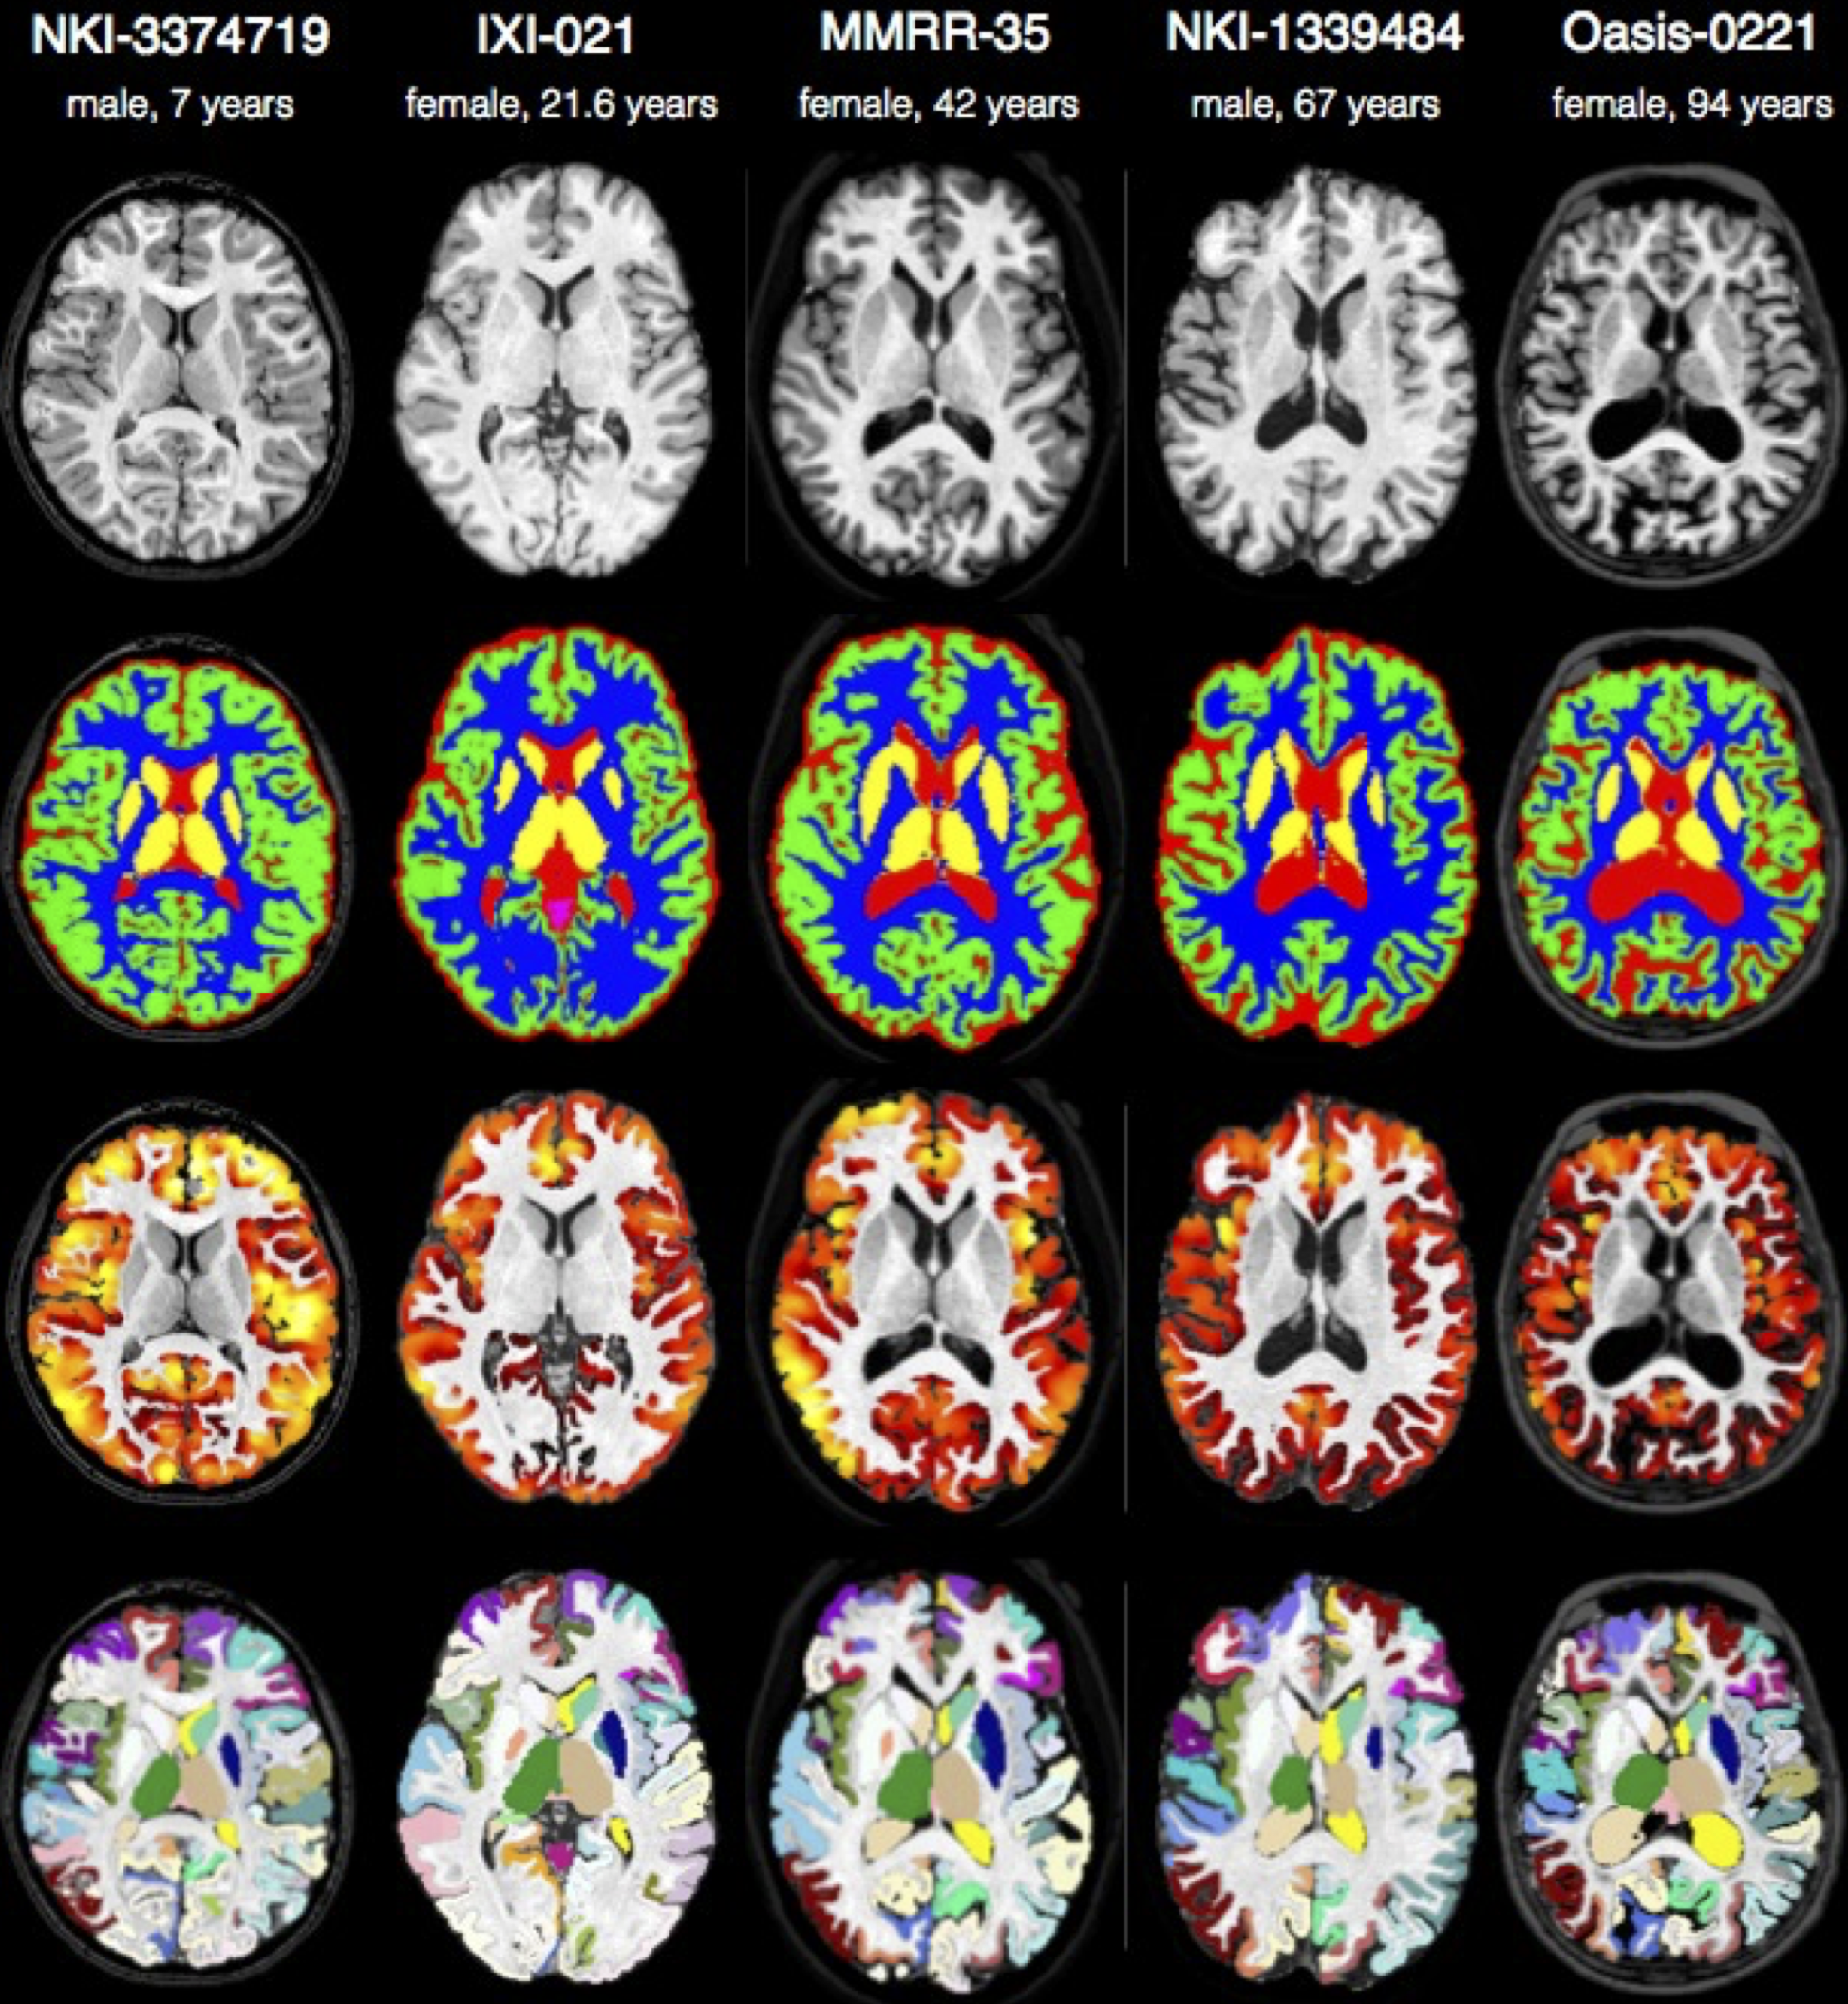

We will analyze multiple modality neuroimaging data with Advanced Normalization Tools (ANTs) version >= 2.1 [1] (http://stnava.github.io/ANTs/). ANTs has proven performance in lifespan analyses of brain morphology [1] and function [2] in both adult [1] and pediatric brain data [2,5,6] including infants [7]. ANTs employs both probabilistic tissue segmentation (via Atropos [3]) and machine learning methods based on expert labeled data (via joint label fusion [4]) in order to maximize reliability and consistency of multiple modality image segmentation. These methods allow detailed extraction of critical image-based biomarkers such as volumes (e.g. hippocampus and amygdala), cortical thickness and area and connectivity metrics derived from structural white matter [13] or functional connectivity [12]. Critically, all ANTs components are capable of leveraging multivariate image features as well as expert knowledge in order to learn the best segmentation strategy available for each individual image [3,4]. This flexibility in segmentation and the underlying high-performance normalization methods have been validated by winning several internationally recognized medical image processing challenges conducted within the premier conferences within the field and published in several accompanying articles [8][9][10][11].